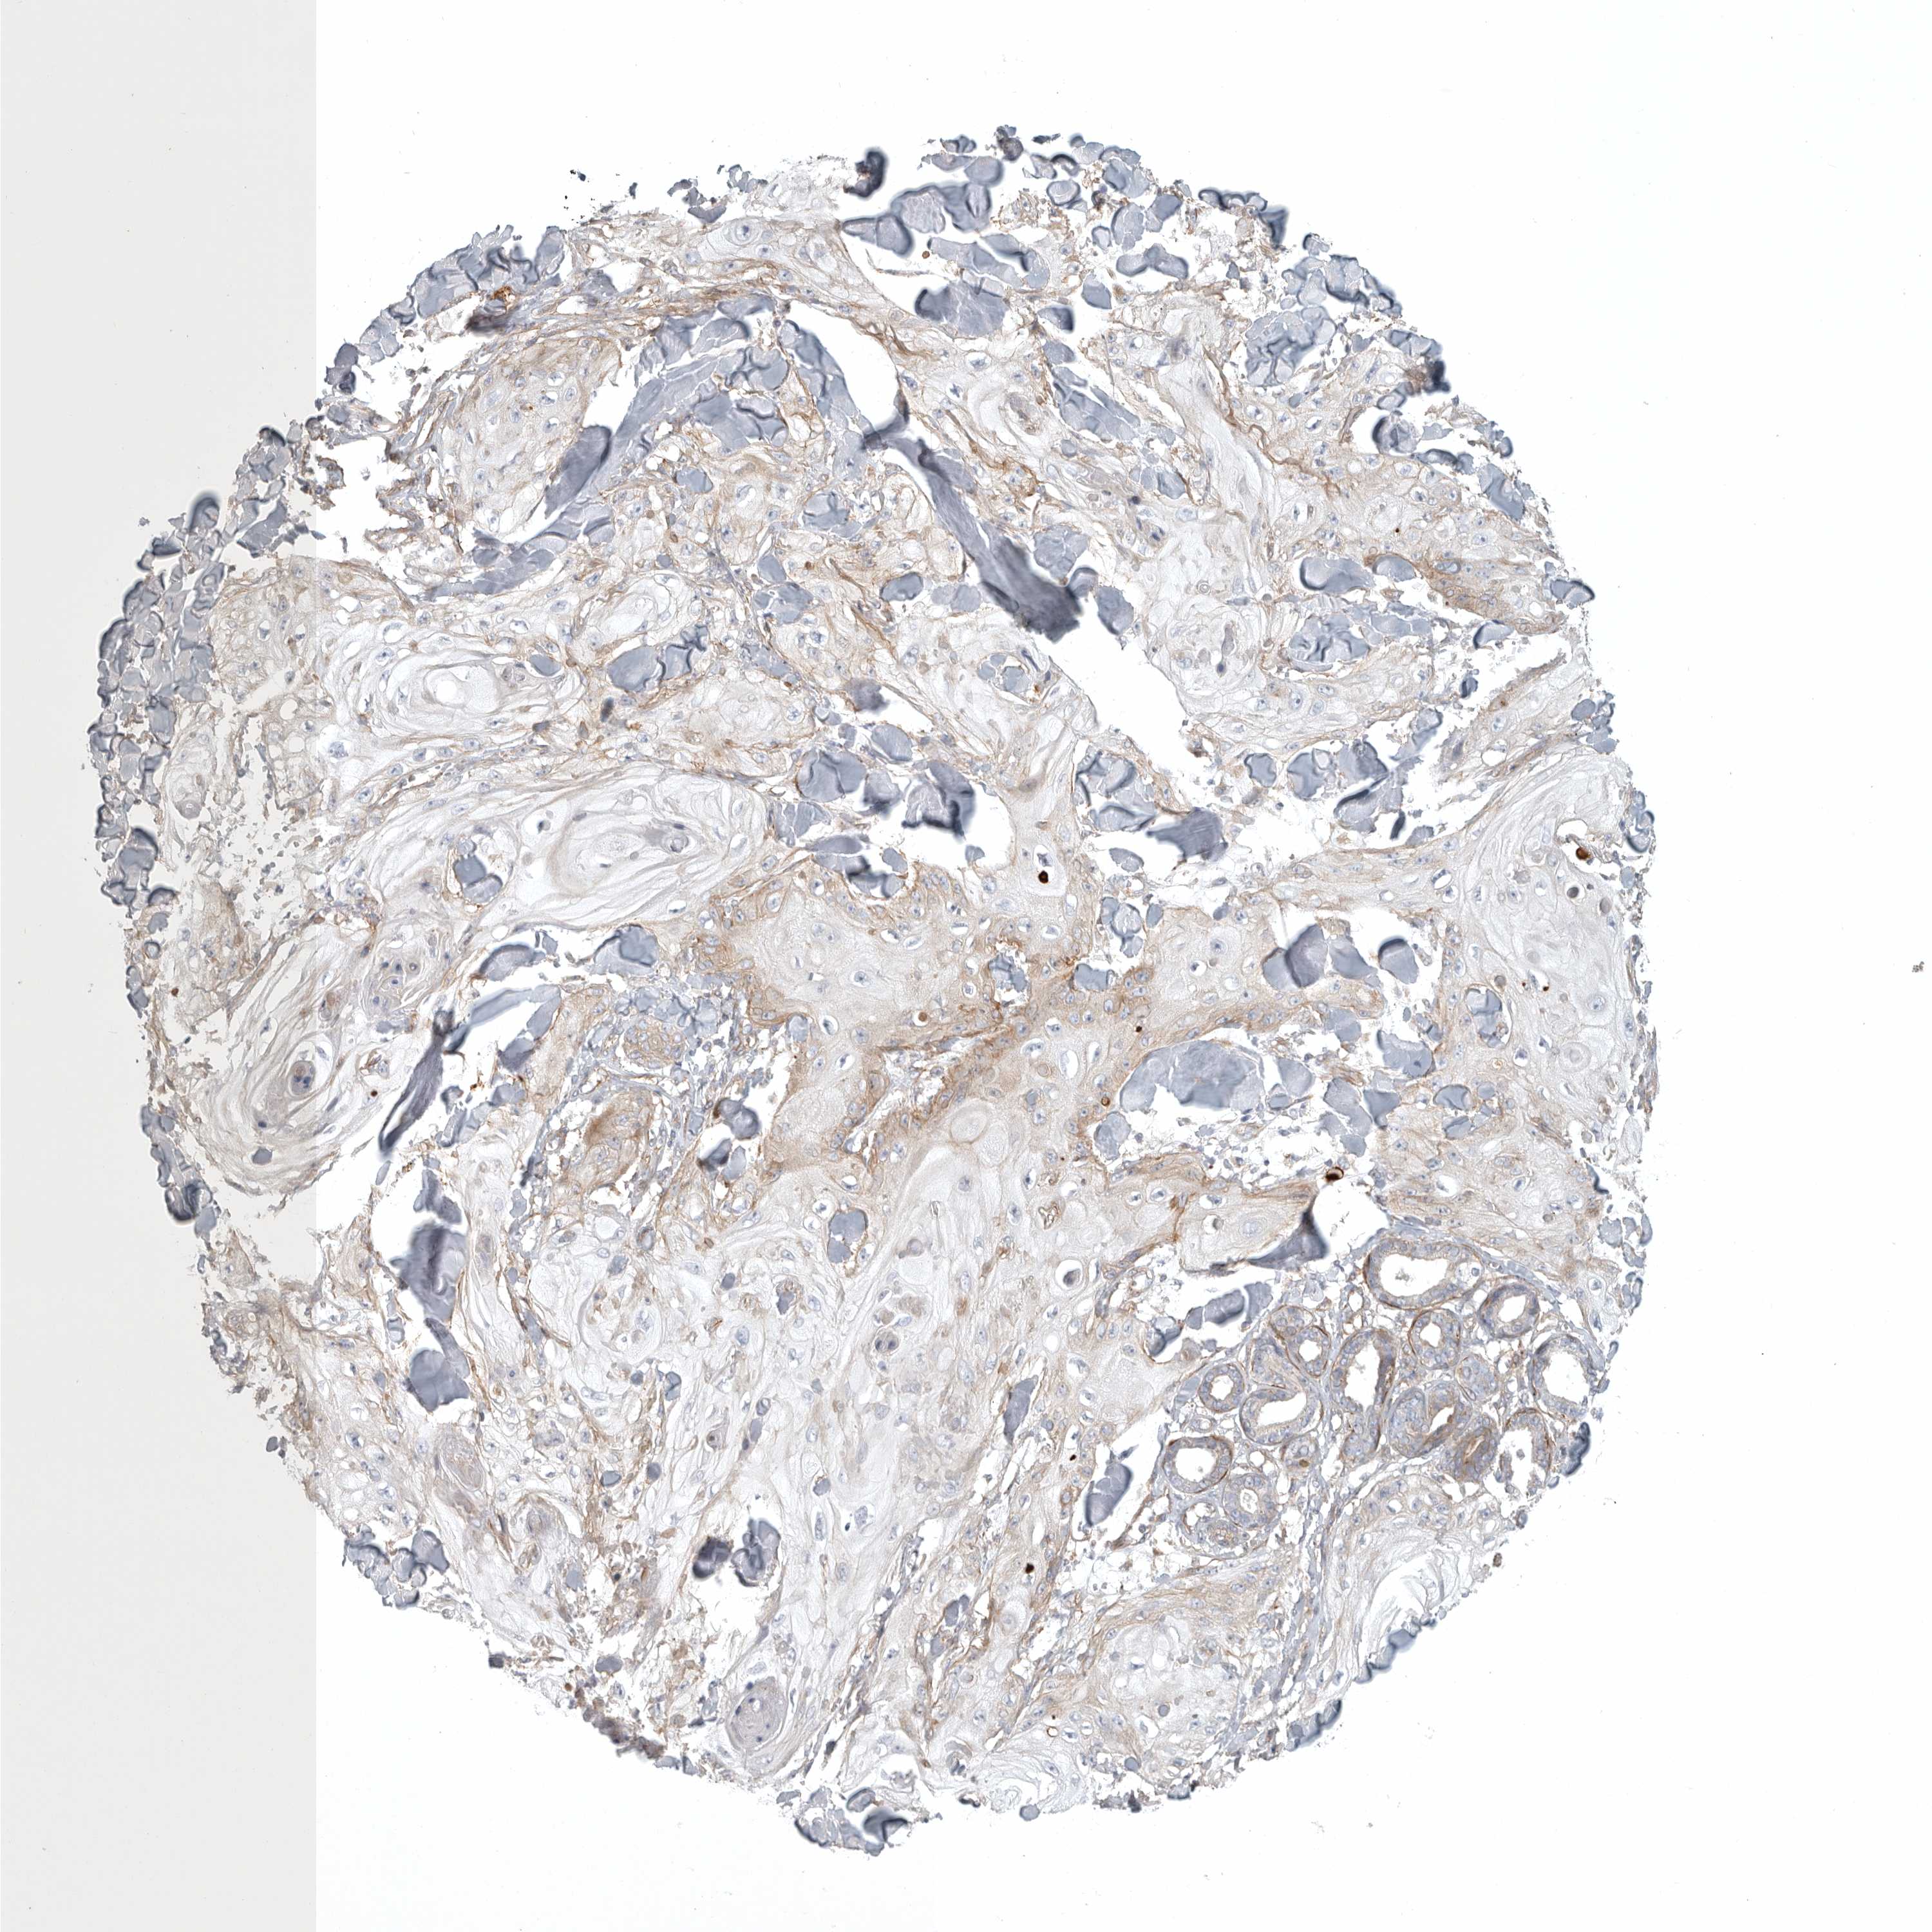

CANCER SKIN CANCER Show tissue menu

Basal cell and squamous cell cancer

SKIN CANCER - Protein expressioni

A mouse-over function shows sample information and annotation data. Click on an image to view it in a full screen mode. Samples can be filtered based on level of antibody staining by selecting one or several of the following categories: high, medium, low and not detected. The assay and annotation is described here.

Each image is clickable and will lead to virtual microscopy that enables deeper exploration of all samples and also displays staining intensity scores, fraction scores and subcellular localization as well as patient and tissue information for each sample.

Antibody HPA023584

Basal cell carcinoma

Squamous cell carcinoma, NOS

Squamous cell carcinoma, metastatic, NOS